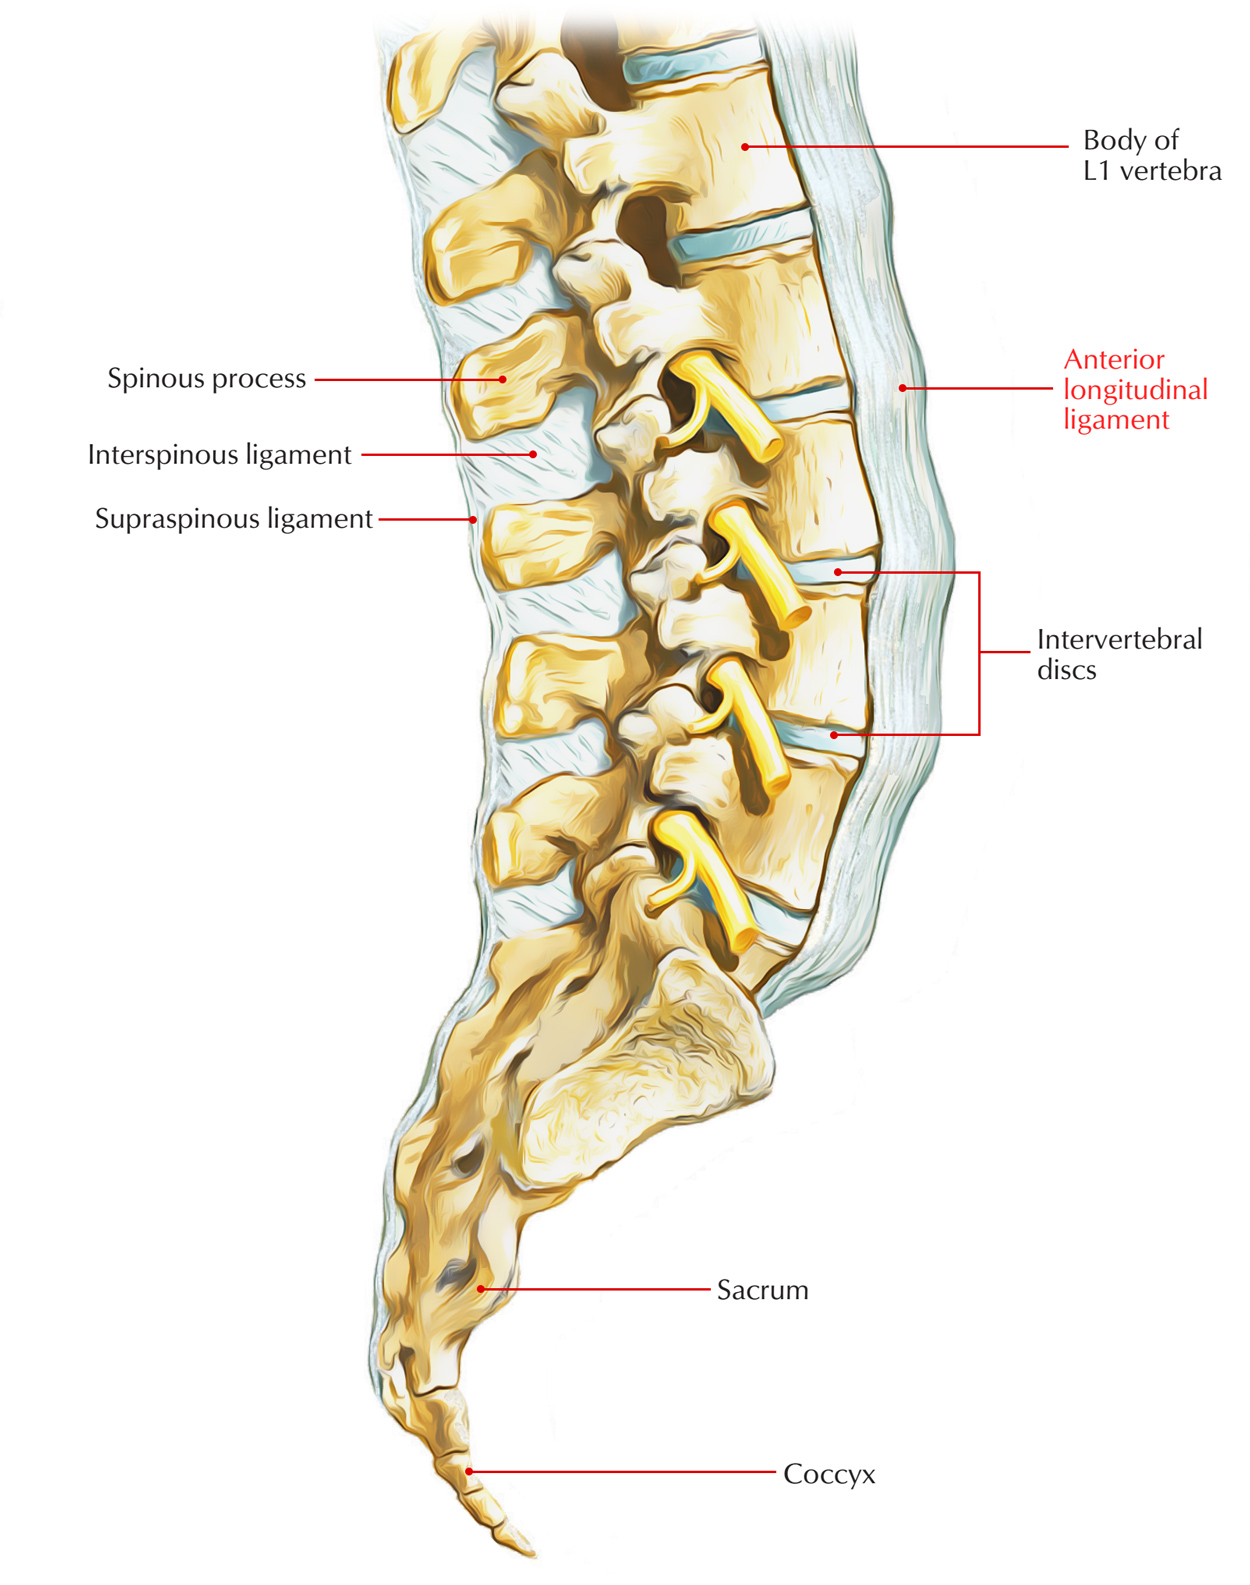

Anatomy of the vertebral column and spinal cord (Chapter 55) - Essential Clinical Anesthesia Review

The vertebral column usually contains three curves. The cervical and lumbar curves are convex anteriorly, and the thoracic curve is convex posteriorly. These curves, together with gravity, barricity of the local anesthetic,